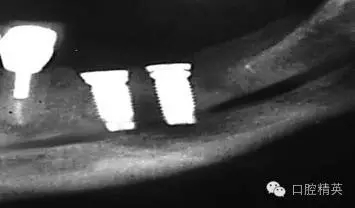

圖7a:6,7號牙種植體(3*15mm)折斷前,從物理學理論上講,種植體骨整合后,基臺螺絲和種植體相連接的支點處是受力時種植體最薄弱的位置。(a)可見6號牙種植體的折斷面,和7號牙種植體上的折裂線(b)。

圖7b:6,7號牙種植體折斷后。

種植體折斷可能發(fā)生于種植體行使功能幾年后,也可能發(fā)生于早期。(圖7a,b)對于圖中這一病例,治療計劃是在對患者的咬合關系,未來修復體理化環(huán)境,患者咀嚼習慣等充分評估后制定的。種植體折斷后,對該病例進行了回顧性病因分析,上了頜架的模型揭示了過長的頜間距離,和嚴重、廣泛的對頜牙磨耗(圖7c,d)。對于這一病例,醫(yī)生仔細評估了所有可得到的回顧性診斷信息,和患者進一步討論交流后,提出了幾個診斷建議和一個過渡性治療方案,其中包括將固定修復改為鑄造可摘局部義齒。

考慮到取出種植體會造成很大的創(chuàng)傷,醫(yī)生提出了一個盡量避免增加創(chuàng)傷風險的折中治療方案。治療為:嚴密縫合關閉6號,7號牙種植體周圍軟組織,將種植體埋入休眠。術后即刻戴入塑料過渡活動義齒,術區(qū)軟組織穩(wěn)定后進行鑄造可摘局部義齒修復。